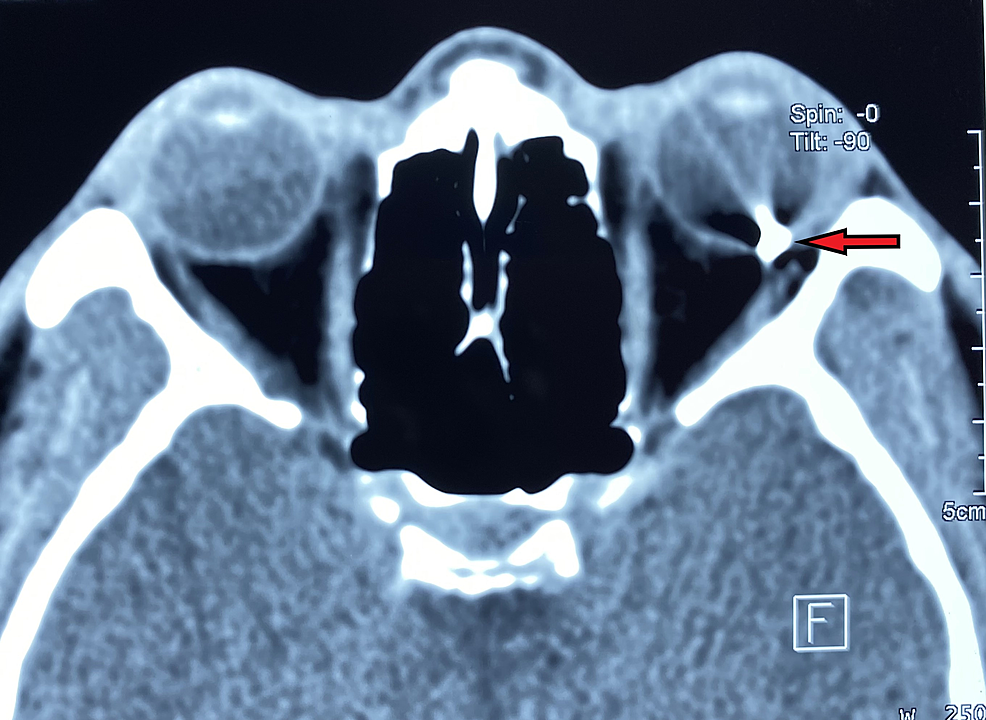

如果外来异物速度更快,力量更大,足够穿透我们的角膜和巩膜而进入眼球并存留于眼球内称为眼内异物。这是一种非常严重的眼外伤。

在开放性眼外伤中,眼内异物伤的发生率为 18%~41%。按异物性质,将眼内异物分为磁性异物和非磁性异物两大类。非磁性异物包括金属异物(铜、锌、铝、镍等)和非金属异物。非金属异物除石块、玻璃、塑料、矿渣、陶瓷外,还包括植物性异物(树枝、竹刺、麦芒、豆类、纸屑等)和动物性异物(睫毛、昆虫肢体、毛发等)。眼内异物破坏了眼球的完整性,容易引起感染性眼内炎、葡萄膜炎、严重视力损害等情况,对眼睛和视功能危害巨大,一旦发生需要尽快就医并手术取出眼内异物。

图表 5 眼眶 CT 显示眼内异物,呈现金属伪影。(图源:参考文献 7)